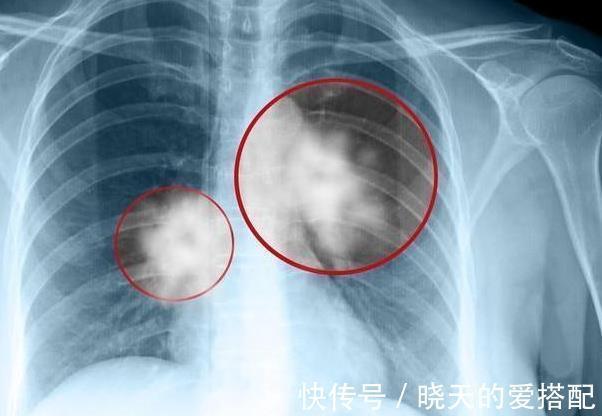

今日话题:46岁男子,不痛不痒,查出肺癌,手上1个异常,提示已到中晚期!

很多人提到肺癌,就会想到胸痛、咳血等异常,但是肺癌跟大多数肿瘤一样,早期症状并不明显,很有可能是不痛不痒。

之后,医生在和老李聊天沟通情况时,发现,老李的手指尖趋于隆起,胀的像鼓槌一样,见此,医生便赶紧让老李进行肺CT检查,果不其然,医生发现了罪魁祸首,是''肺癌'',并且已到了中晚期。

经了解,老李是个不折不扣的烟民,已经抽烟二十余年了,不久前自己就开始胸闷咳嗽,手指变得发鼓,可不曾想,这竟是肺癌征兆啊!

医生提醒:肺癌不痛不痒,可手上1个标记,提示已到中晚期!